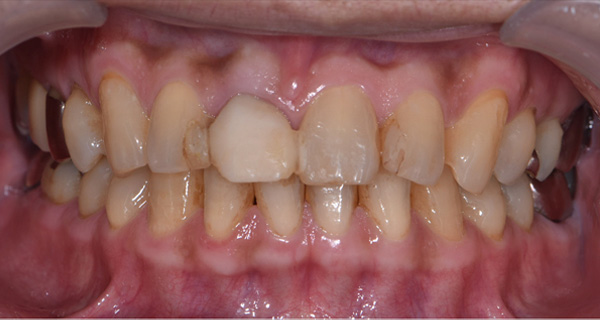

BEFORE

| 年代・性別 | 50代 男性 |

|---|---|

| 主訴 | 右上下の歯が痛い |

| 治療期間 | 約12ヶ月 |

| 費用 | 2,500,000円 |

| 治療内容 | インプラント、骨造成、結合組織移植、セラミック修復 |

| 治療に伴うリスク | インプラント周囲炎 セラミックの破折、脱離 |

*キャンセルポリシーをご一読のうえご予約ください